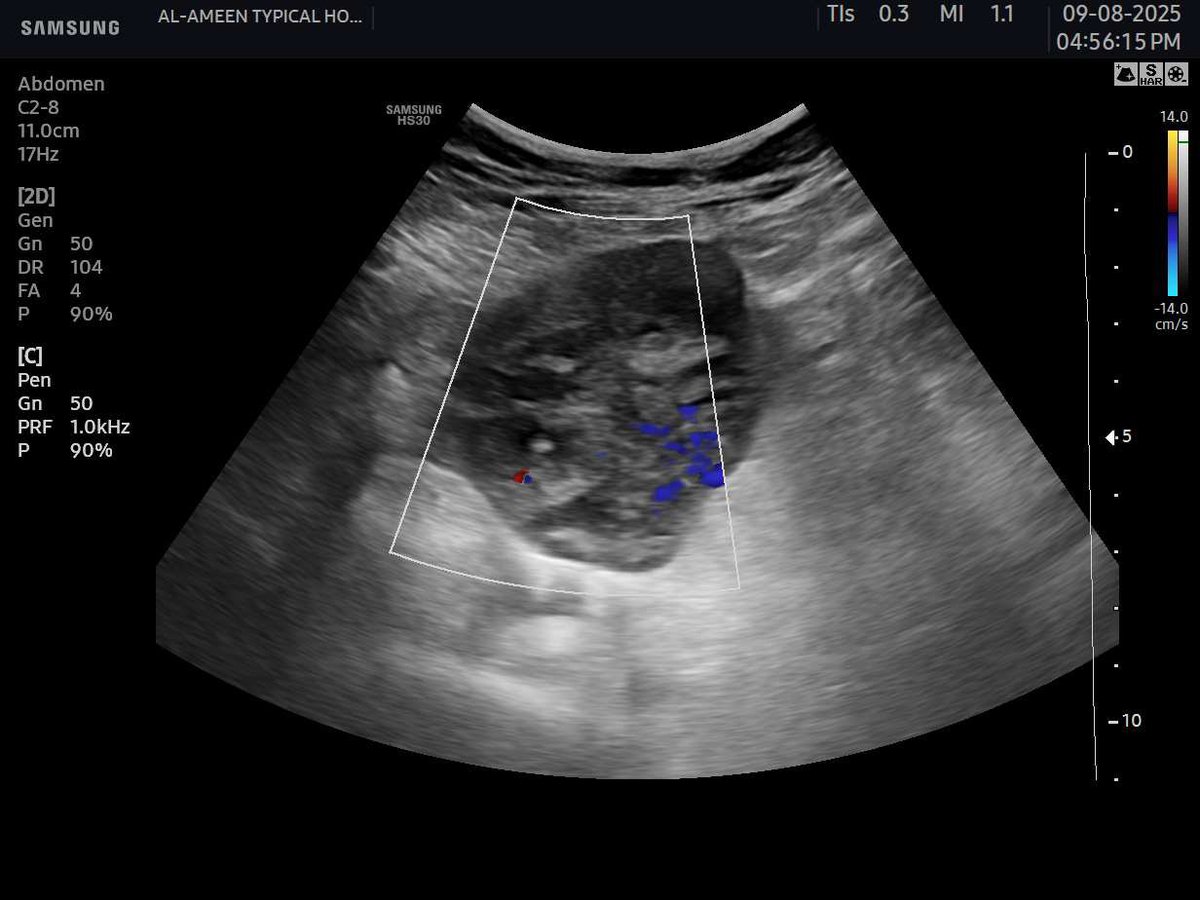

This 50 years female pt came with acute pain in the epigastrium and jaundice. Your opinion? Name of the sonographic sign?? Area of scan :RUQ. #EchoTech

This 50 years female pt came with acute pain in the epigastrium and jaundice. Your opinion? Name of the sonographic sign?? Area of scan :RUQ. #EchoTech